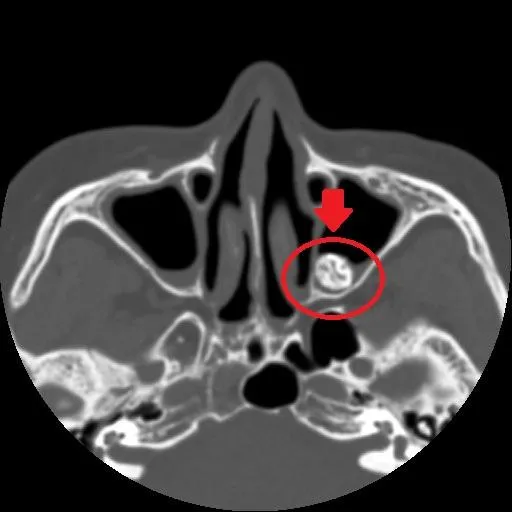

頭痛

鼻竇炎

鼻涕倒流

血絲鼻涕

亞大附屬醫院

鼻竇異生齒